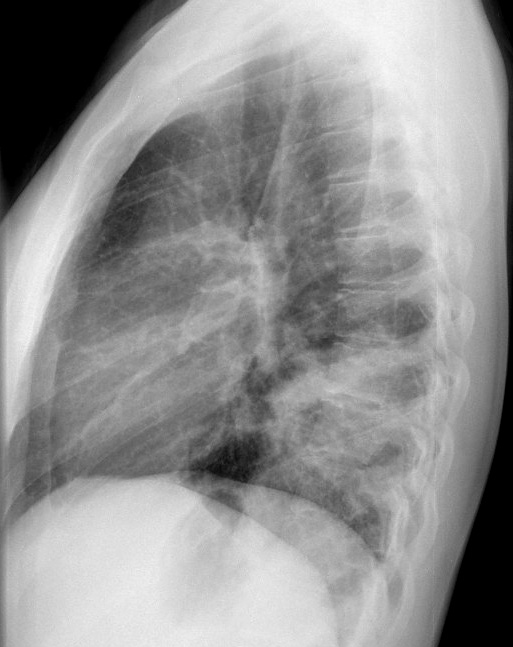

Gallery Pneumonia Case 6 RLL pneum Lat

Case 6 RLL pneum Lat